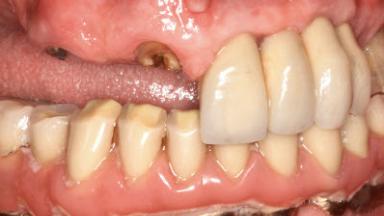

A 66-year-old patient presented because of retention loss of the tooth-supported FDP in the right maxilla (x-13-x-11). The mandibular full-arch implant-supported reconstruction (x-i34-i33-x-x-x-x-i43-i44-x) had suffered extreme wear. His medical history revealed high blood pressure, controlled with anti-hypertensive medication. The patient was a light smoker (2 to 3 cigarettes per day). The existing reconstructions had been performed alio loco about five years previously. That treatment had taken an extensive amount of time, and as early as during the fabrication of the reconstructions, multiple complications had occurred with the provisionals.